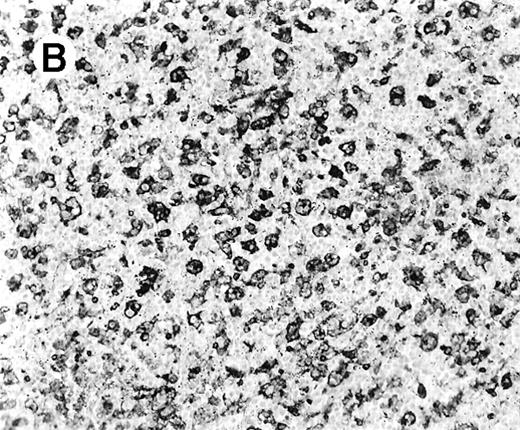

The immunophenotypic features and molecular data are summarized in Table 2. Immunophenotyping was performed on the spleen or liver or both in all cases. The infiltrate in all cases was composed predominantly of CD3+ T cells (Figure3A). CD20 stained attenuated residual B-cell areas in the spleen and only rare scattered B cells were identified within the liver (Figure 3B). Staining for CD4 and CD8 showed that the infiltrate was CD8+ in 2 cases (Figure4A), CD4+ in 2 cases (Figure5A), and in the remaining 2 cases CD4+ and CD8+ cells were noted in approximately equal numbers without clear subset predominance. CD4 highlighted the erythrophagocytic histiocytes (Figure 4B). The lymphocytes in all cases expressed βF1 and TIA-1+ (Figure 4C and D) and were CD56−.

Staining for CD4 and CD8 in spleen from case 2.

(A) The lymphoid infiltrate in the spleen is predominantly CD8+. (B) Staining for CD4 highlights erythrophagocytic histiocytes, whereas the lymphocytes are negative. (C) The small lymphocytes express TIA-1. (D) They are BF1+ and are strongly EBER-1+ (E) (immunoperoxidase stained, hematoxylin counterstained, × 200).